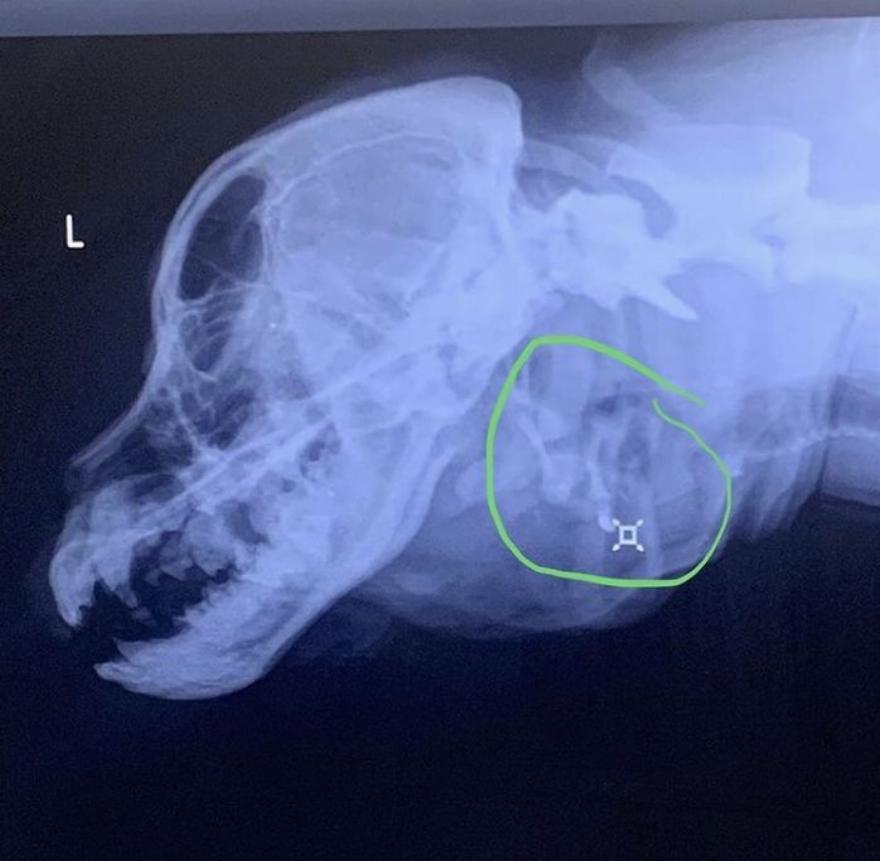

Κάναμε κι άλλες ακτινογραφίες του κρανίου της Toad. Τώρα που έχουμε τη Toad για μεγάλο χρονικό διάστημα και μάθαμε για τα προβλήματά της περισσότερα από ό,τι όταν την πρωτογνωρίσαμε, είμαστε σε θέση να κατανοήσουμε τις ακτινογραφίες λίγο καλύτερα. Η πρώτη εικόνα δείχνει πόσο παράξενο είναι το σχήμα του κρανίου της. Έχει ένα επιπλέον τροχιακό οστό γύρω από την κόγχη των ματιών της, πιθανότατα από το κρανίο του δίδυμου που απορρόφησε στη μήτρα, το οποίο κάνει το κρανίο της πολύ βολβοειδές. Ο κόκκινος κύκλος δείχνει δύο σετ υοειδών οστών. Το κίτρινο δείχνει ότι οι σπόνδυλοι δεν είναι συνδεδεμένοι όπως θα έπρεπε. Ο πράσινος κύκλος δείχνει την επιπλέον τραχεία της, η οποία δεν έχει σχηματιστεί πλήρως.